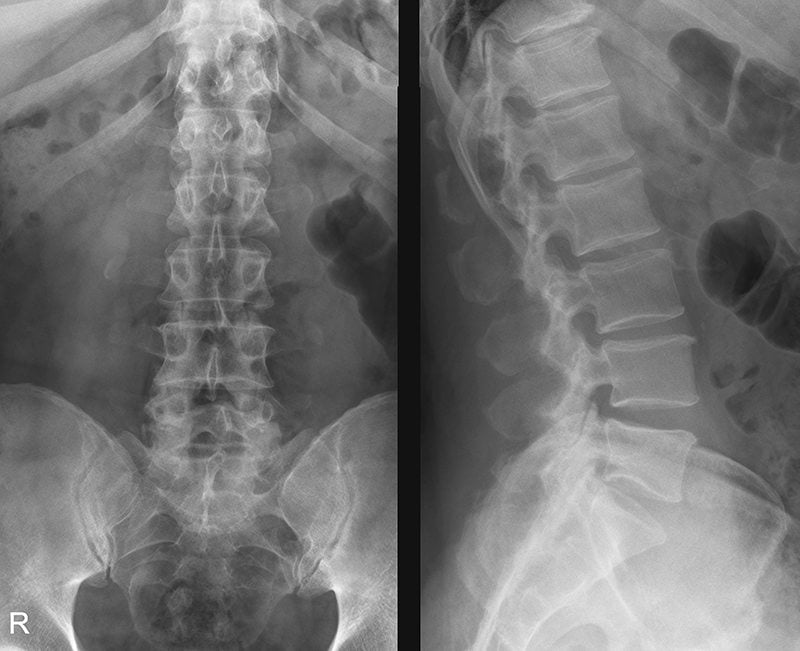

Рентген пояснично-крестцового отдела – это простой и доступный метод диагностики, позволяющий выявлять опухоли, переломы, деформации, воспалительные и дегенеративные заболевания позвоночника. Рентгенографию можно сделать в любом медицинском учреждении.

Рентгенологическое исследование визуализирует только костные структуры позвоночника. Связки, нервы, сосуды, мягкие ткани, межпозвонковые диски (МПД) и суставы на рентгенограммах не видны. Из-за этого исследование уступает по информативности магнитно-резонансной томографии (МРТ). Последнюю назначают, если традиционная рентгенография не позволяет получить нужную информацию о состоянии позвоночника.

Что показывает рентген пояснично-крестцового отдела позвоночника

Большинство рентгенологических признаков, которые выявляют при исследовании, являются неспецифическими. Это значит, что они не позволяют достоверно поставить точный диагноз. Чтобы подтвердить заболевание, врачи должны учитывать анамнестические данные, клинические симптомы и результаты других методов исследования.

Большинство болезней диагностируют по их косвенным признакам (например, разрыв связок – по смещению позвонков при функциональном исследовании, остеохондроз – по наличию остеофитов и уменьшению расстояния между позвонками). Трудностей в диагностике обычно не возникает при переломах, которые хорошо визуализируются на рентгенограммах.

Для многих заболеваний позвоночника характерна похожая рентгенологическая картина. Например, уменьшение межпозвонковых щелей и субхондральный склероз могут указывать на остеохондроз, болезнь Бехтерева, спондилоартрит, ревматоидный артрит, протрузии или грыжи межпозвоночных дисков.

Дефекты, которые выявляются при рентгенографии:

- остеофиты — костные разрастания по краям позвонков. Внешне выглядят, как крючки;

- изменение расстояния между дисками. Является следствием дегенеративных или травматических повреждений МПД. Выглядит, как сужение щели между отдельными позвонками;

- субхондральный склероз и остеосклероз. Характеризуются патологическим разрастанием и уплотнением костной ткани рядом с МПД и/или в области межпозвонковых суставов;

- оссификация передней продольной связки. Развивается из-за отложения солей кальция. Внешне выглядит, как уплотнение на передней поверхности позвонков. Обычно указывает на спондилез;

- остеопения. Проявляется снижением плотности костной ткани, которую легко заметить на снимках. Может говорить о системном остеопорозе или туберкулезном поражении позвоночного столба. Остеопения – один из косвенных признаков деформирующего остеоартроза.